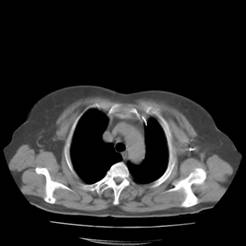

典型病例1:患者鞠xx,女,68岁,住院号:488141,因左胸痛1月余入院。2015年3月31日胸部增强CT示:左肺下叶2.5cmx2.8cm占位,左侧第三前肋骨溶骨性转移、形成厚约3cm肿块,左侧腋窝淋巴结2.1cmx4.1cm及前纵膈淋巴结转移。患者于2015年4月1日经CT引导下穿刺活检、病理证实为左肺下叶腺癌。于2015年4月5日对其采用125I放射性粒子置入治疗。治疗3个月随访,患者胸痛缓解,左肺下叶原发病灶消失,粒子聚集;左侧第三前肋骨基本恢复正常形态;前纵膈淋巴结消失,粒子聚集;左侧腋窝淋巴结缩小2/3。目前患者生活质量良好,可从事一般家务劳动。

术前CT片: